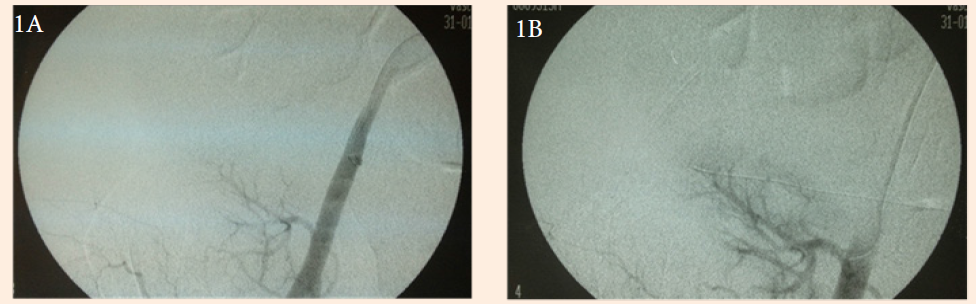

A 46-year old woman underwent living donor kidney transplantation on 01/30/2012. The donor was her sister and the donated kidney had an inferior polar artery that was anastomosed to the main renal artery. The recipient showed good diuresis during the early hours, followed by an abrupt decrease of urine output. An ultrasound (US) revealed a renal-iliac resistance index and intrarenal resistance index of 1.34 and 0.5, respectively. However, intrarenal pulsatility determined by US Doppler showed a parvus et tardus pulse pattern suggesting thrombosis of the intrarenal arteries or renal artery stenosis. A diagnostic arteriography indicated less than 24 hours postoperatively revealed a full anastomosis contrast without stenosis, but a faint contrast filling of the intrarenal arteries (Figure 1A). These arteries were selectively catheterized and 15 mg of recombinant tissue plasminogen activator (rTPA) was injected for intrarenal thrombolysis (Figure 1B). There was some improvement in the intrarenal filling pattern, but there was also an area of spasm (stenosis) of the renal artery 1 cm from the anastomosis. Balloon angioplasty was performed, followed by an intra luminal post anastomotic renal artery stent (Figure 1C). An immediate control arteriography showed excellent perfusion (Figure 1D). Serum creatinine was reduced from 6.3 to 1.22 mg/dL within five days and remained at 1.16 mg/dL during the late postoperative period (Figure 2). The patient continues to have normal renal function and normal US Doppler. The only complication was an 11.3 by 5.2 cm graft site hematoma treated with percutaneous drainage using a Jackson-Pratt (Blake) drain.

Figure 1a Initial arteriography showing impaired postanastomotic perfusion.

Figure 1B Selective renal artery thrombolysis with 15 mg rTPA.

Figure 1C Renal artery spasm (stenosis) before stenting.

Figure 1D Final arteriography showing normal renal transplant perfusion.